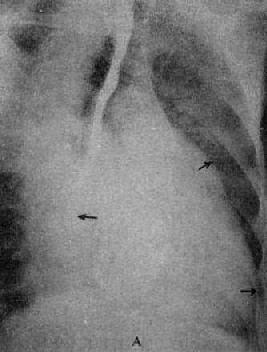

图3-2-15 二尖瓣狭窄

A.右前斜位:右心室增大,肺动脉段突出(↑),心前间隙变窄(↑),左心房轻度增大;B.后前位:心增大,呈二尖瓣型,右心室增大,肺动脉段突出,左心耳增大,出现第三弓(↓),有肺瘀血表现;C.左前斜位:右心室增大,左心房增大不明显;左心室不增大。